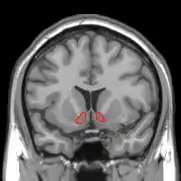

Research studies using functional magnetic resonance imaging (or fMRI) have found the increased activity of certain brain parts when one experiences the sensation of tickle. An increased cerebral blood flow in the somatosensory cortex - or S1 - is shown in response to tickle induced by an external stimulus (McGlone et al., 2002). This particular area of the cortex is the primary receiver of sensory inputs from the body relayed via the thalamus (Hine & Martin, 2015). The S1 occupies the postcentral gyrus and is devoted to process information from the somatic receptors (Colman, 2008). When one receives an externally administered tactile stimulus that produces the tickle sensation, the S1 shows an increased activity, suggesting that tickle is indeed a fundamental sensation of the skin.

The neural root of ticklish laughter in humans has been found to be within the limbic system. A study using an fMRI revealed a significant role of hypothalamic activity in evoking ticklish laughter (Wattendorf et al., 2013). It was found that tickling followed by involuntary laughter activated parts within the limbic system, which are the lateral hypothalamus and amygdala, as well as the parietal operculum and the right side of the cerebellum (Wattendorf et al., 2013). Tickling was also found to activate the higher-order sensory regions which has been associated with the conscious perception of both skin contact and pain (Watterndorf et al., 2013), which may explain the defensive reaction people engage in when being tickled.